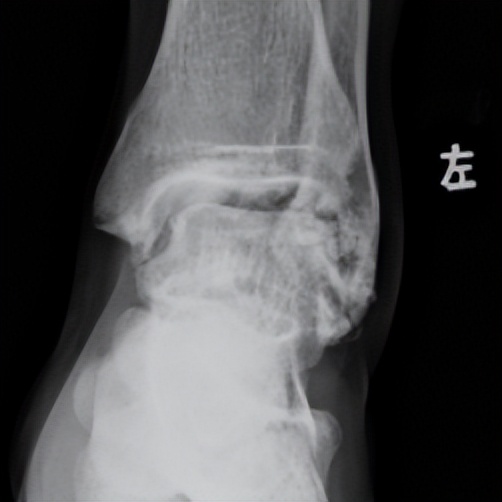

10年前,林先生扭伤了脚部踝关节,经过四处求医,反复治疗,仍未见好转,被多家医院诊断为“滑膜炎”。后来,他通过微信公众号了解到相关案例,联系了广东省第二人民医院(以下简称“省二医”)关节骨科运动医学组组长何河北医生进行线上沟通,何河北医生认为,林先生的症状可能是踝关节慢性不稳,便建议其来医院就诊。

林先生来到省二医后,何河北医生为其进行了详细查体,检查后确诊为踝关节不稳+滑膜软骨瘤。

何河北制定了详细的手术方案,为患者开展踝关节镜下滑膜软骨瘤取出术+距腓前韧带重建术。他从患者踝关节中取出32颗“珍珠”(关节游离体),然后进行踝关节外侧韧带重建。

▲术前可见踝关节前方有大量“珍珠”。